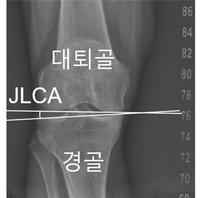

- 2026 ¹Ð¶ó³ë¡¤ÄÚ¸£Æ¼³ª´ãÆäÃÊ µ¿°è¿Ã¸²ÇÈ °³¸·À» ¾ÕµÎ°í, ¡®½ºÅ° ¿©Á¦¡¯·Î ºÒ¸®´Â ¸°Áö º»(42¡¤¹Ì±¹)ÀÇ ¹«¸ ºÎ»óÀÌ ÀçÁ¶¸íµÇ°í ÀÖ´Ù. Àü¹æ½ÊÀÚÀδ밡 ¿ÏÀüÈ÷ ÆÄ¿µÈ »óȲ¿¡¼µµ ¿Ã¸²ÇÈ ÃâÀü¿¡ ´ëÇÑ °ÇÑ ÀÇÁö¸¦ µå·¯..